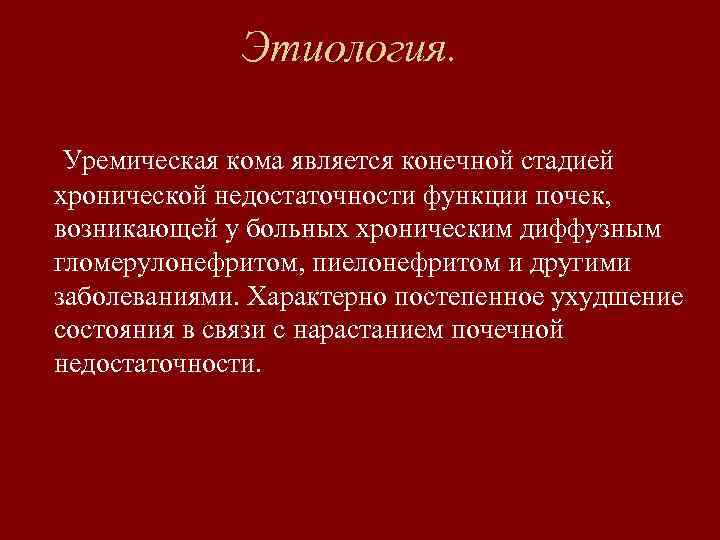

Этиология. Уремическая кома является конечной стадией хронической недостаточности функции почек, возникающей у больных хроническим диффузным гломерулонефритом, пиелонефритом и другими заболеваниями. Характерно постепенное ухудшение состояния в связи с нарастанием почечной недостаточности.

Этиология. Уремическая кома является конечной стадией хронической недостаточности функции почек, возникающей у больных хроническим диффузным гломерулонефритом, пиелонефритом и другими заболеваниями. Характерно постепенное ухудшение состояния в связи с нарастанием почечной недостаточности.